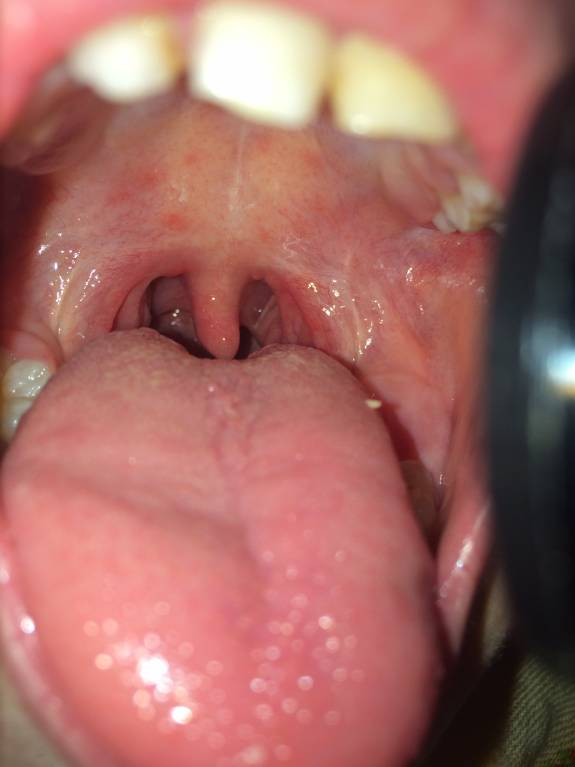

2. Начало Ангины фолликулярной???

3. Четыре дня назад ребёнок перенёс вирусное заболевание, перенёс с жаропонижающими. Осталось красное горло и кашель небольшой. Сегодня с утра сказал что горло болит, при осмотре мною была найдена маленькая крупинка белого цвета.

Крупинка справа, но поймать не сумела.

По описанию, состояния болезни нет. По фото, проявлений ангины нет.